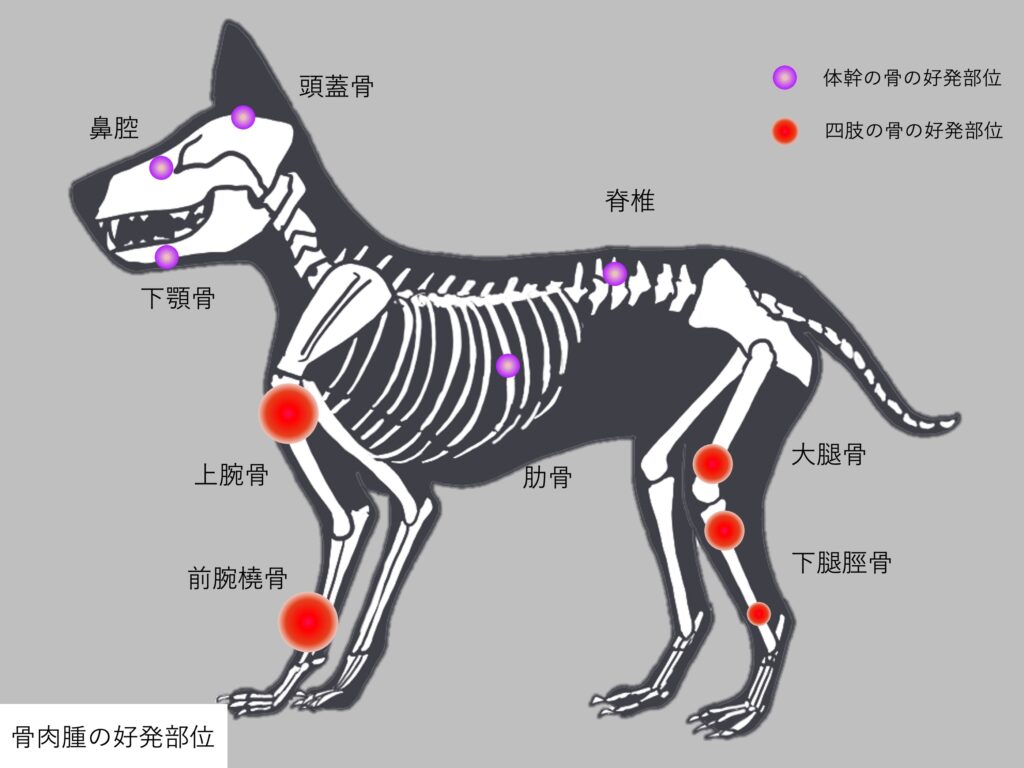

発生部位

骨肉腫は体重のかかる四肢に発生することが多く骨肉腫発生全体の75%を占めると言われています。

特に前肢上腕骨の肩側、前腕橈骨の手首側の骨幹端が最も好発部位となり、他にも後肢の大腿骨、下腿脛骨それぞれの膝側の骨幹端にも発生します。

しかし、日本で多い15kg以下の小型犬では四肢以外の発生も多く、下顎骨、上顎骨、脊椎、頭蓋骨、肋骨、鼻腔内といった体幹の骨での発生が59%を占めると言われています。

また、乳腺といった骨組織以外での発生も稀に見られます。